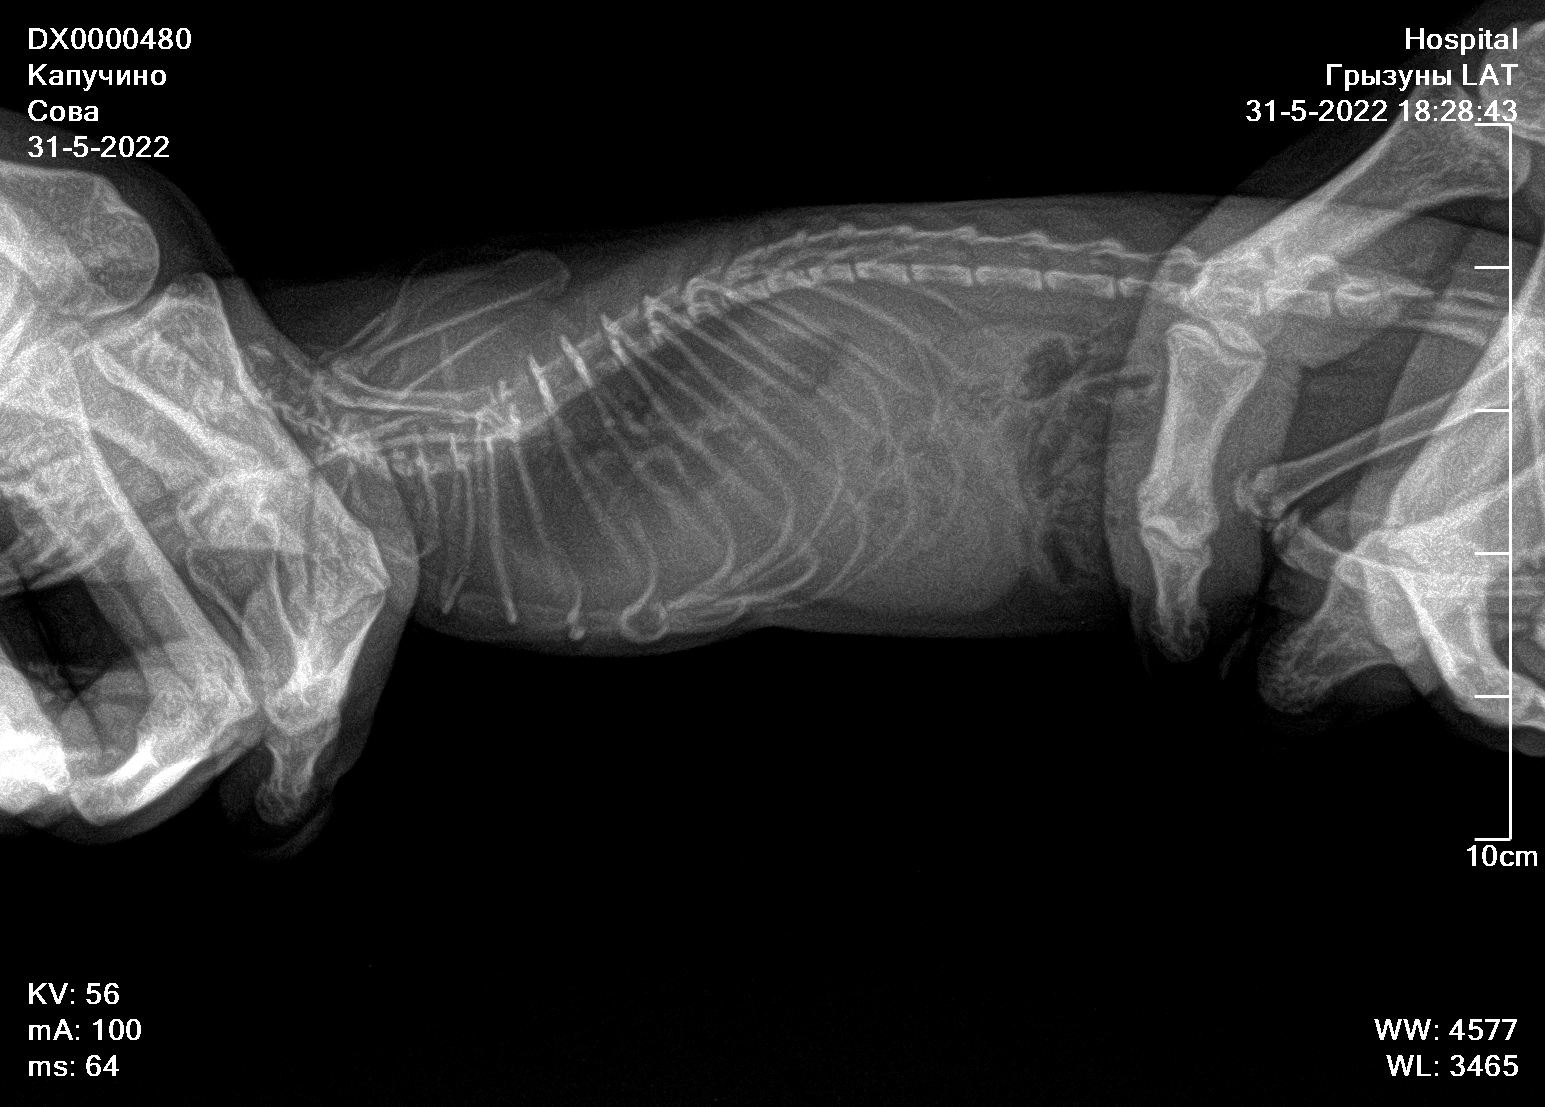

Город Волгодонск, девочка, 1 год. Тяжёлое дыхание, сделали рентген. В вк в домике крысы отдали снимки рентгенологу. С самого первого поста там прошёл почти месяц. По рентгену диагностировали большое количество жидкости в грудной клетке, структура легких уплотнена. Прописали Тилозин 0.05мл 2 раза в день на 5 дней посмотреть динамику. Сказали, что процесс необратим и лечить нечем. Находил на форуме похожие случаи, подскажите, что сделать, чтобы хотя бы стабилизировать и поддерживать состояние крысы? Она очень активная, с аппетитом всё хорошо. Только очень тяжёлое дыхание.